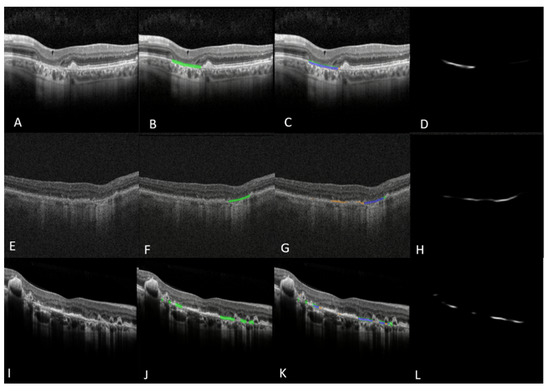

2.4. GA Ground Truth Mask Generation for En Face Model

3.2. The En Face OCT-Based GA and Hypertransmission Defect Detector and Quantifier